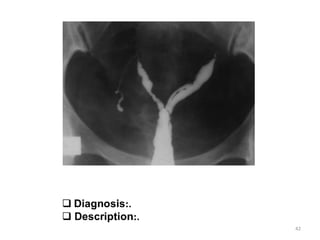

 Diagnosis:.

 Description:.

2 uterus

2 cervix

2 vagina

1 vagina